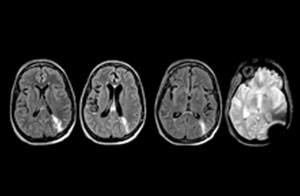

A range of protocol sheets was developed to help ensure that referring physicians order the most appropriate MRI exam. The optimized MRI protocols also include 3D contrast-enhanced imaging, allowing neurosurgeons to comfortably use the isotropic data in the operating room while performing stereotaxic surgery.

For Dr. Karis, the next goals for the neuro ED include converting the exams for acute stroke and TIA patients from CT to MRI, offering an alternative management option for these patients. Also, collaboration between other departments is currently underway, encouraging the performance of targeted exams with the ED MRI. These improvements in workflow and faster turnaround times may result in further reductions in scanning time.